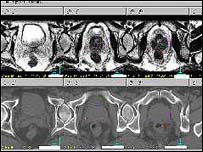

البته تنها سطح PSA در آزمايش خون فرد نمايانگر ابتلا به سرطان پروستات نيست. در برخی از موارد عفونت و يا ”بزرگی خوش ‌خيم“ حجم غده پروستات می ‌تواند سبب افزايش ميزان PSA در خون شود. از اين رو، ترکيب معاينه مقعد توأم با آزمايش تعيين سطح PSA از طريق خون روش دقيق‌تری برای تشخيص سرطان پروستات است و برای اطمينان بيشتر، در مراحل بعدی آزمايشات ديگری مانند تصويرنگاری باز آوای مغناطيسی (MRI)، سونوگرافی (Ultrasound)، توموگرافی کامپيوتری (CT SCAN) و نمونه ‌برداری از غده (Biopsy) نيز انجام می‌گيرد.